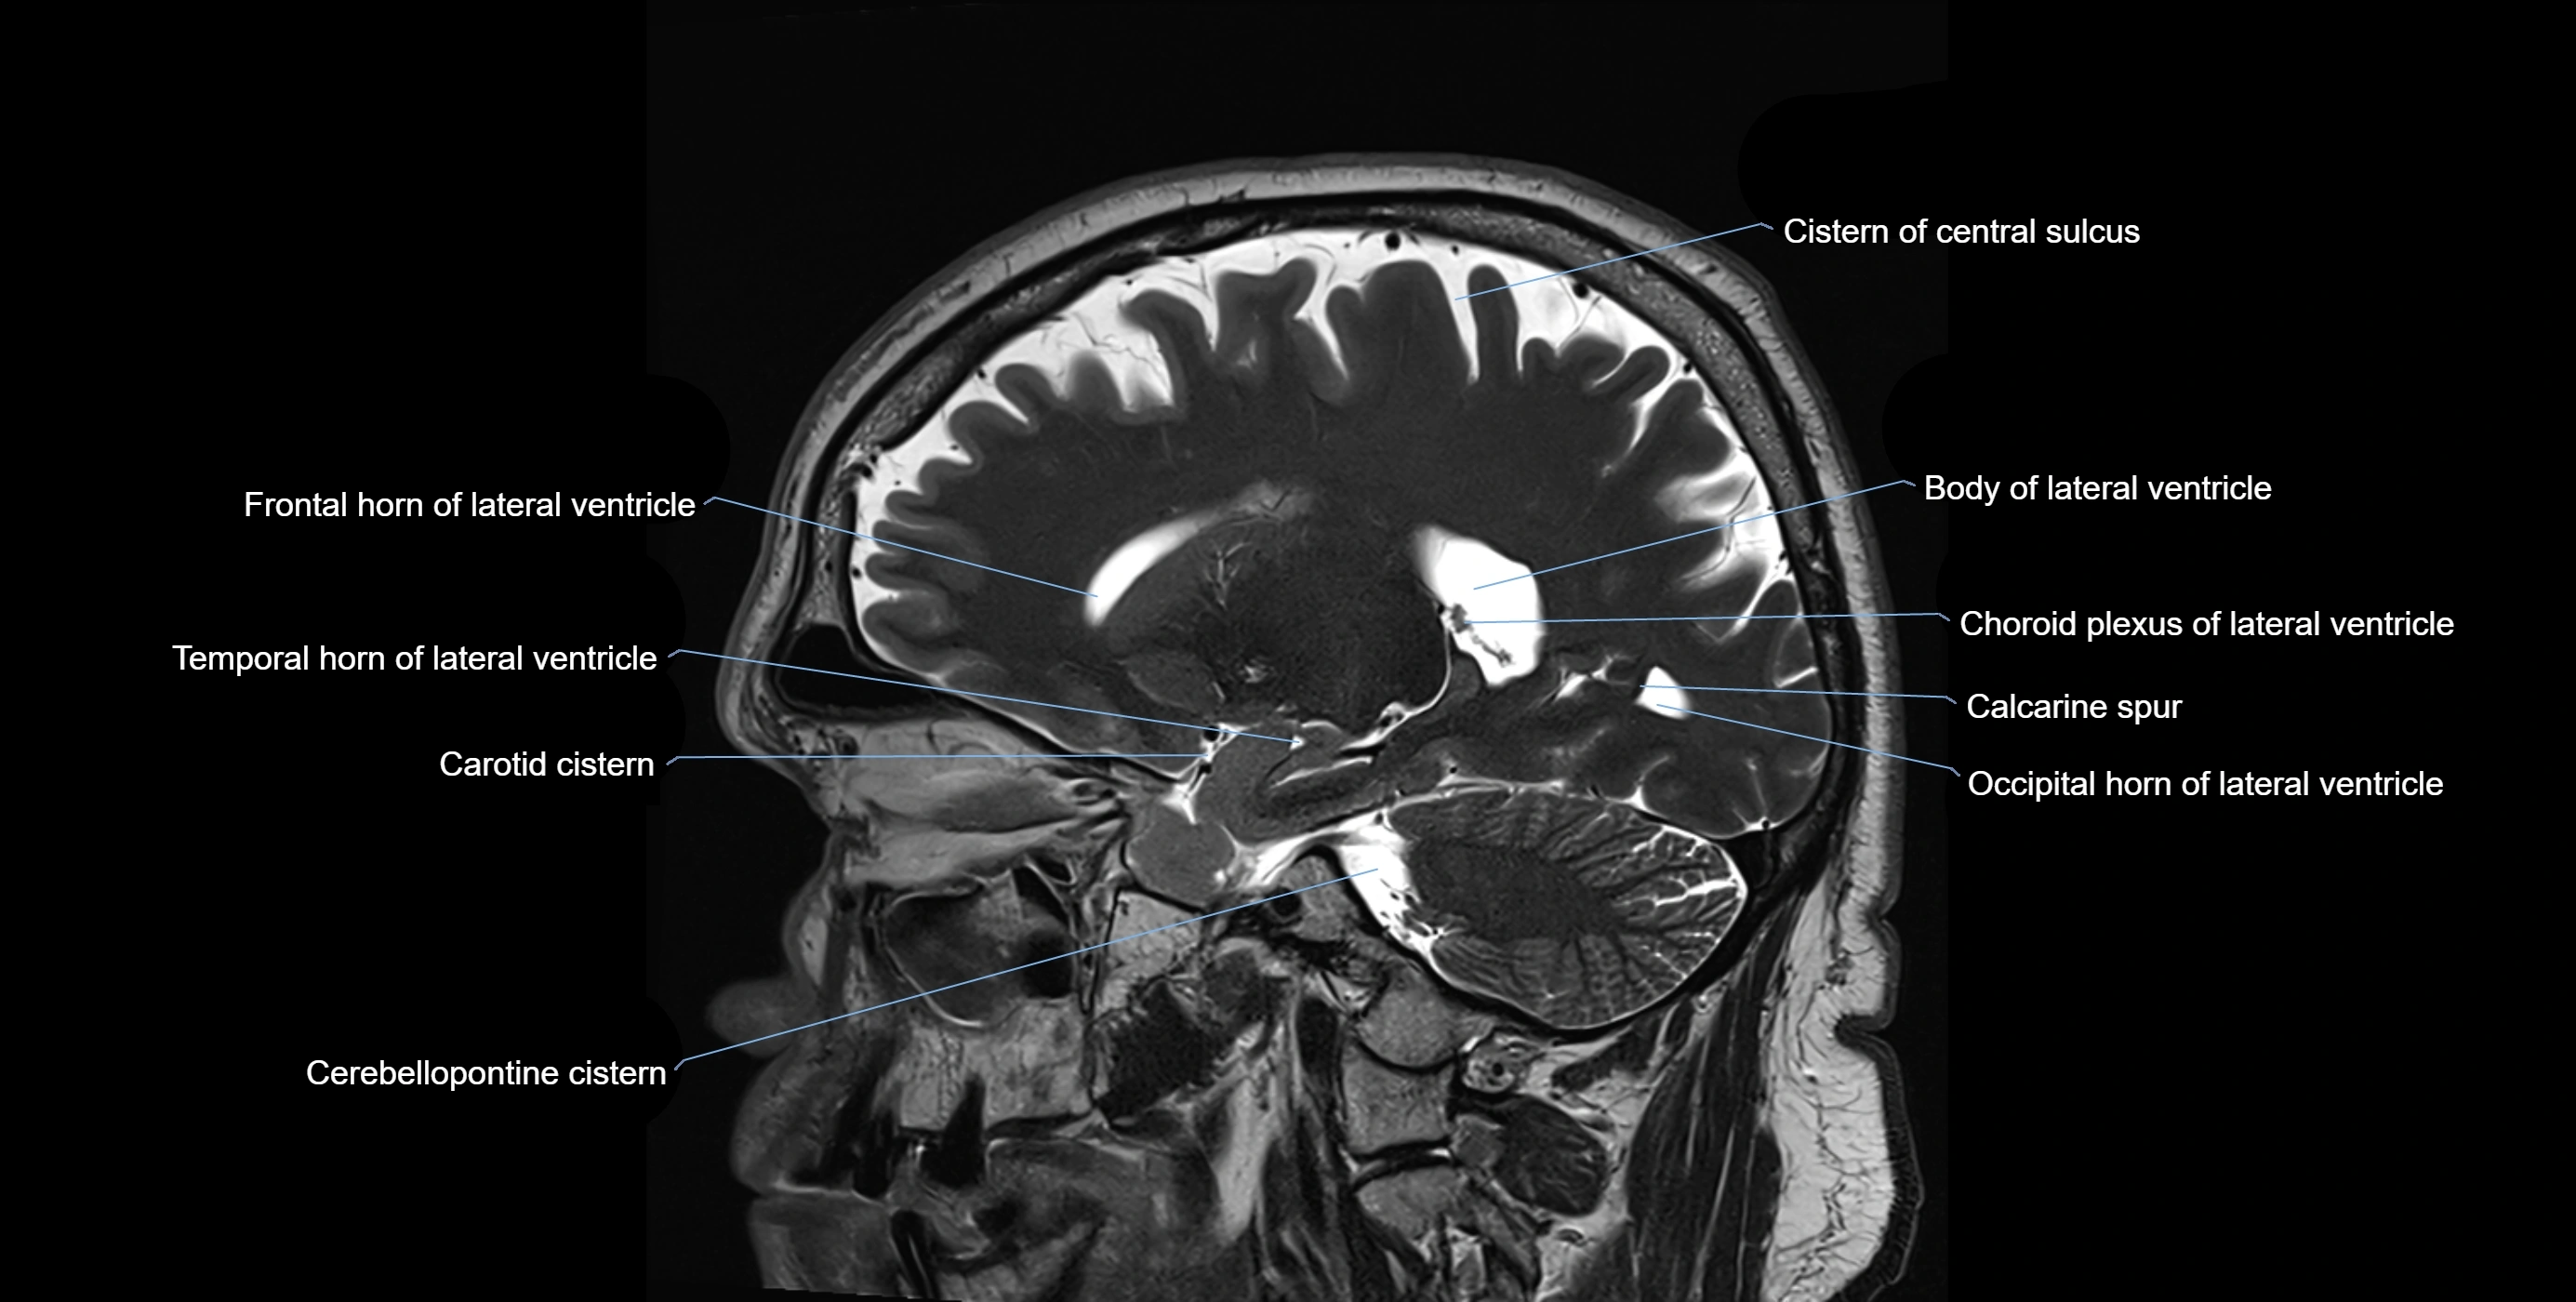

MRI images

image